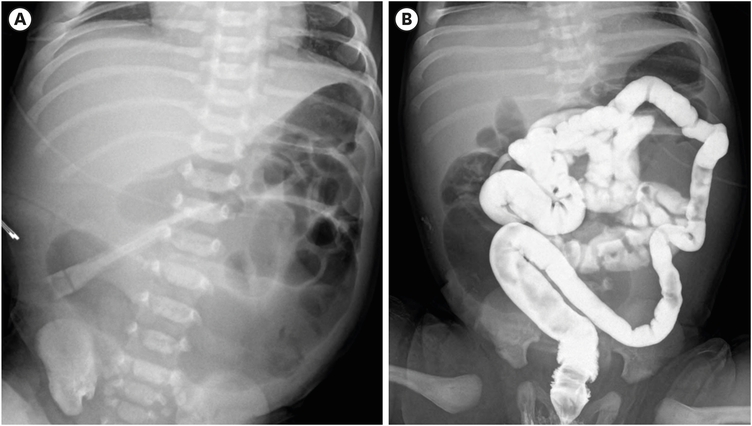

In a normally active neonate, the swallowed air usually reaches the proximal bowel within an hour and the distal small bowel within three hours [21]. In most cases, plain abdominal radiographs (supine and lateral view) demonstrate the presence of intestinal obstruction in patients. Proximal jejunal atresia may present as only a small amount of air-fluid level in the proximal dilated bowel and a gasless abdomen beyond the atresia. The more distal the atresia, the more severe the abdominal distension, with more distended bowel loops and air-fluid levels. In ileal atresia, the bowel just proximal to the atresia is much more dilated and may show more air-fluid levels, which may require differential diagnosis with meconium ileus or total colonic aganglionosis. In these cases, a contrast enema can be helpful (Fig. 5) [22]. In 12% of JIA, plain radiographs show peritoneal calcification, indicating meconium peritonitis [23]. The giant cystic meconium peritonitis is associated with late intrauterine bowel perforation, where the perforated intestine and meconium form an encapsulated mass (pseudocyst) (Fig. 6) [24]. In a survey by KAPS in 2010, meconium peritonitis was reported in 22.1% of JIA (12.5% in jejunal atresia and 31.5% in ileal atresia) [4].

Fig. 5

Ileal atresia. (A) A plain abdominal radiograph taken 10 hours after birth shows a distal small bowel obstruction. (B) A contrast enema reveals a small colon that does not fill the dilated loops of the bowel.